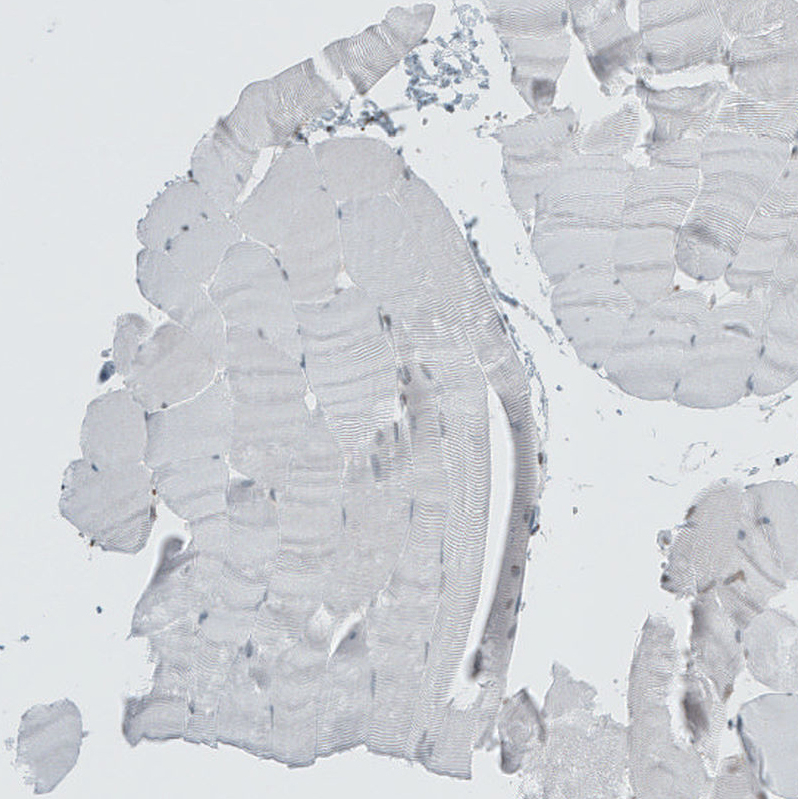

Immunohistochemical staining of human Skin shows moderate nuclear positivity in keratinocytes.